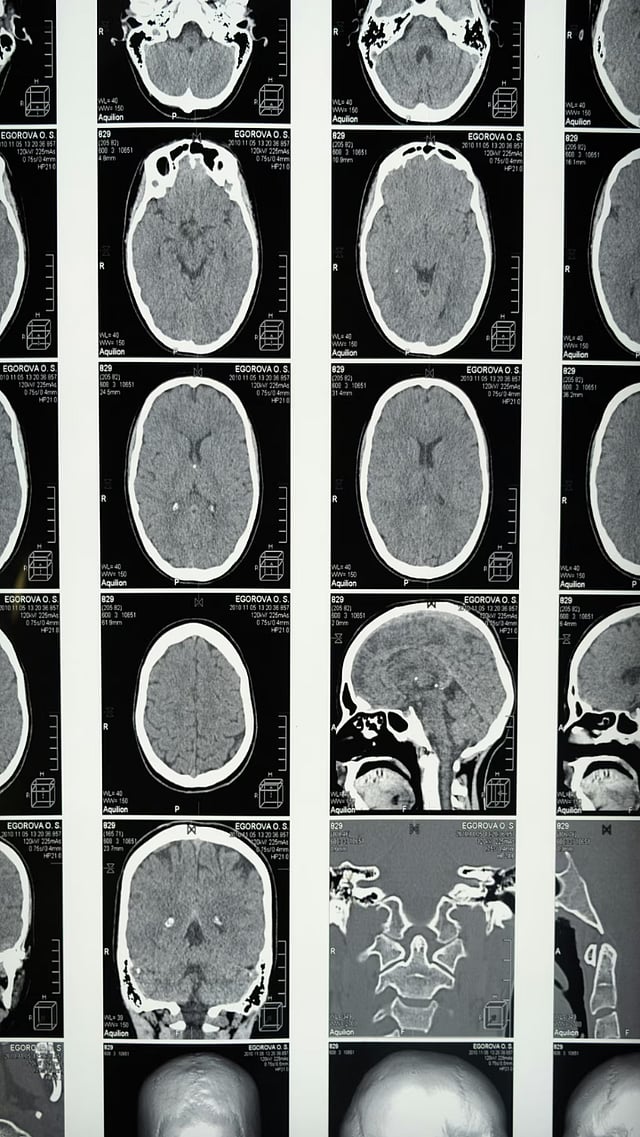

ब्रेन हॅमरेज

बिघडलेल्या जीवनशैलीमुळे ब्रेन हॅमरेजसारखा धोकादायक आजार होणंही आता सामान्य गोष्ट झाली आहे.

ब्रेन हॅमरेज कोणत्याही वयातील व्यक्तीला कधीही होऊ शकतो. मात्र रात्री ब्रेन हॅमरेज होण्याचा धोका आणखी वाढतो.